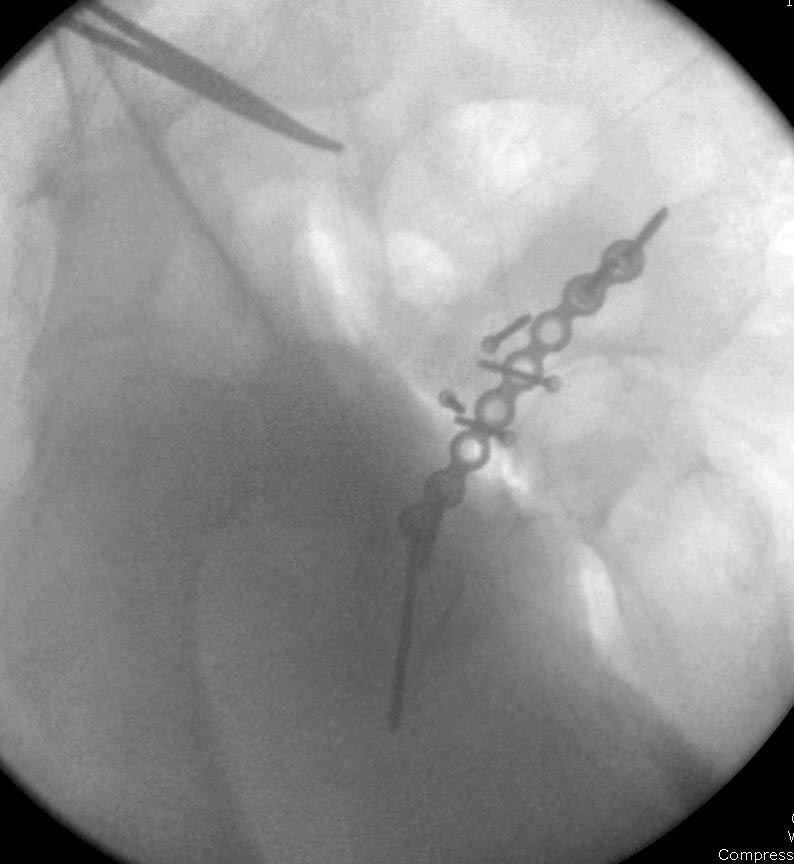

7:30 начало операции, больной на спине, попытка репозиции после анестезии N3, укладка больного на боку, доступ Kocher- Langenbeck, состояние седалищнего нерва около 2.5см кровоподтек, через joistick головка бедра приподнята, освобовождение сустава, фрагмент заднего края более 3х4 см репонирован на свое место. После промывания

сустава, репозиция вывиха (N4), фиксация фрагмента 2.7(4) мм шурупами и допольнительно реконструктивной пластиной на 8 дырок, фиксация 3.5мм шурупами проксимально и дистально.

Интраоперционные N5 косая запирательная и N6 подвздошный снимок

Работаем вместе с хирургами-травматологами (в штатах все травмированные больные поступают, как больные хирургической службы, ортопед выступает в качестве консультанта), т.е. мы даем рекомендации о проведении профилактики тромбоза, совместно решаем о проведении фильтра - вена кава фильтр (см. приложение).

Если вена кава фильтр, хирурги проводят эту процедуру, а медикаментозную профилактику назначаем сами.